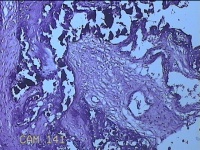

胎盘组织

性别

女

年龄

30岁

临床诊断

妊娠合并中度贫血

一般病史

停经39+2周,B超检查发现羊水偏少6小时。

标本名称

大体所见

灰白暗红色胎盘组织16.5x14.5x3.5㎝一个,表面光滑,血管突出,颜色发暗,绒毛面结节状,有轻度糜烂,暗红色,有少许凝血块,切面见绒毛内有暗红色血液渗出,边缘蜕膜可见多个小血肿,脐带39x1.8x0.3㎝,螺旋状扭曲,切断脐带,见脐血管内有凝血块。